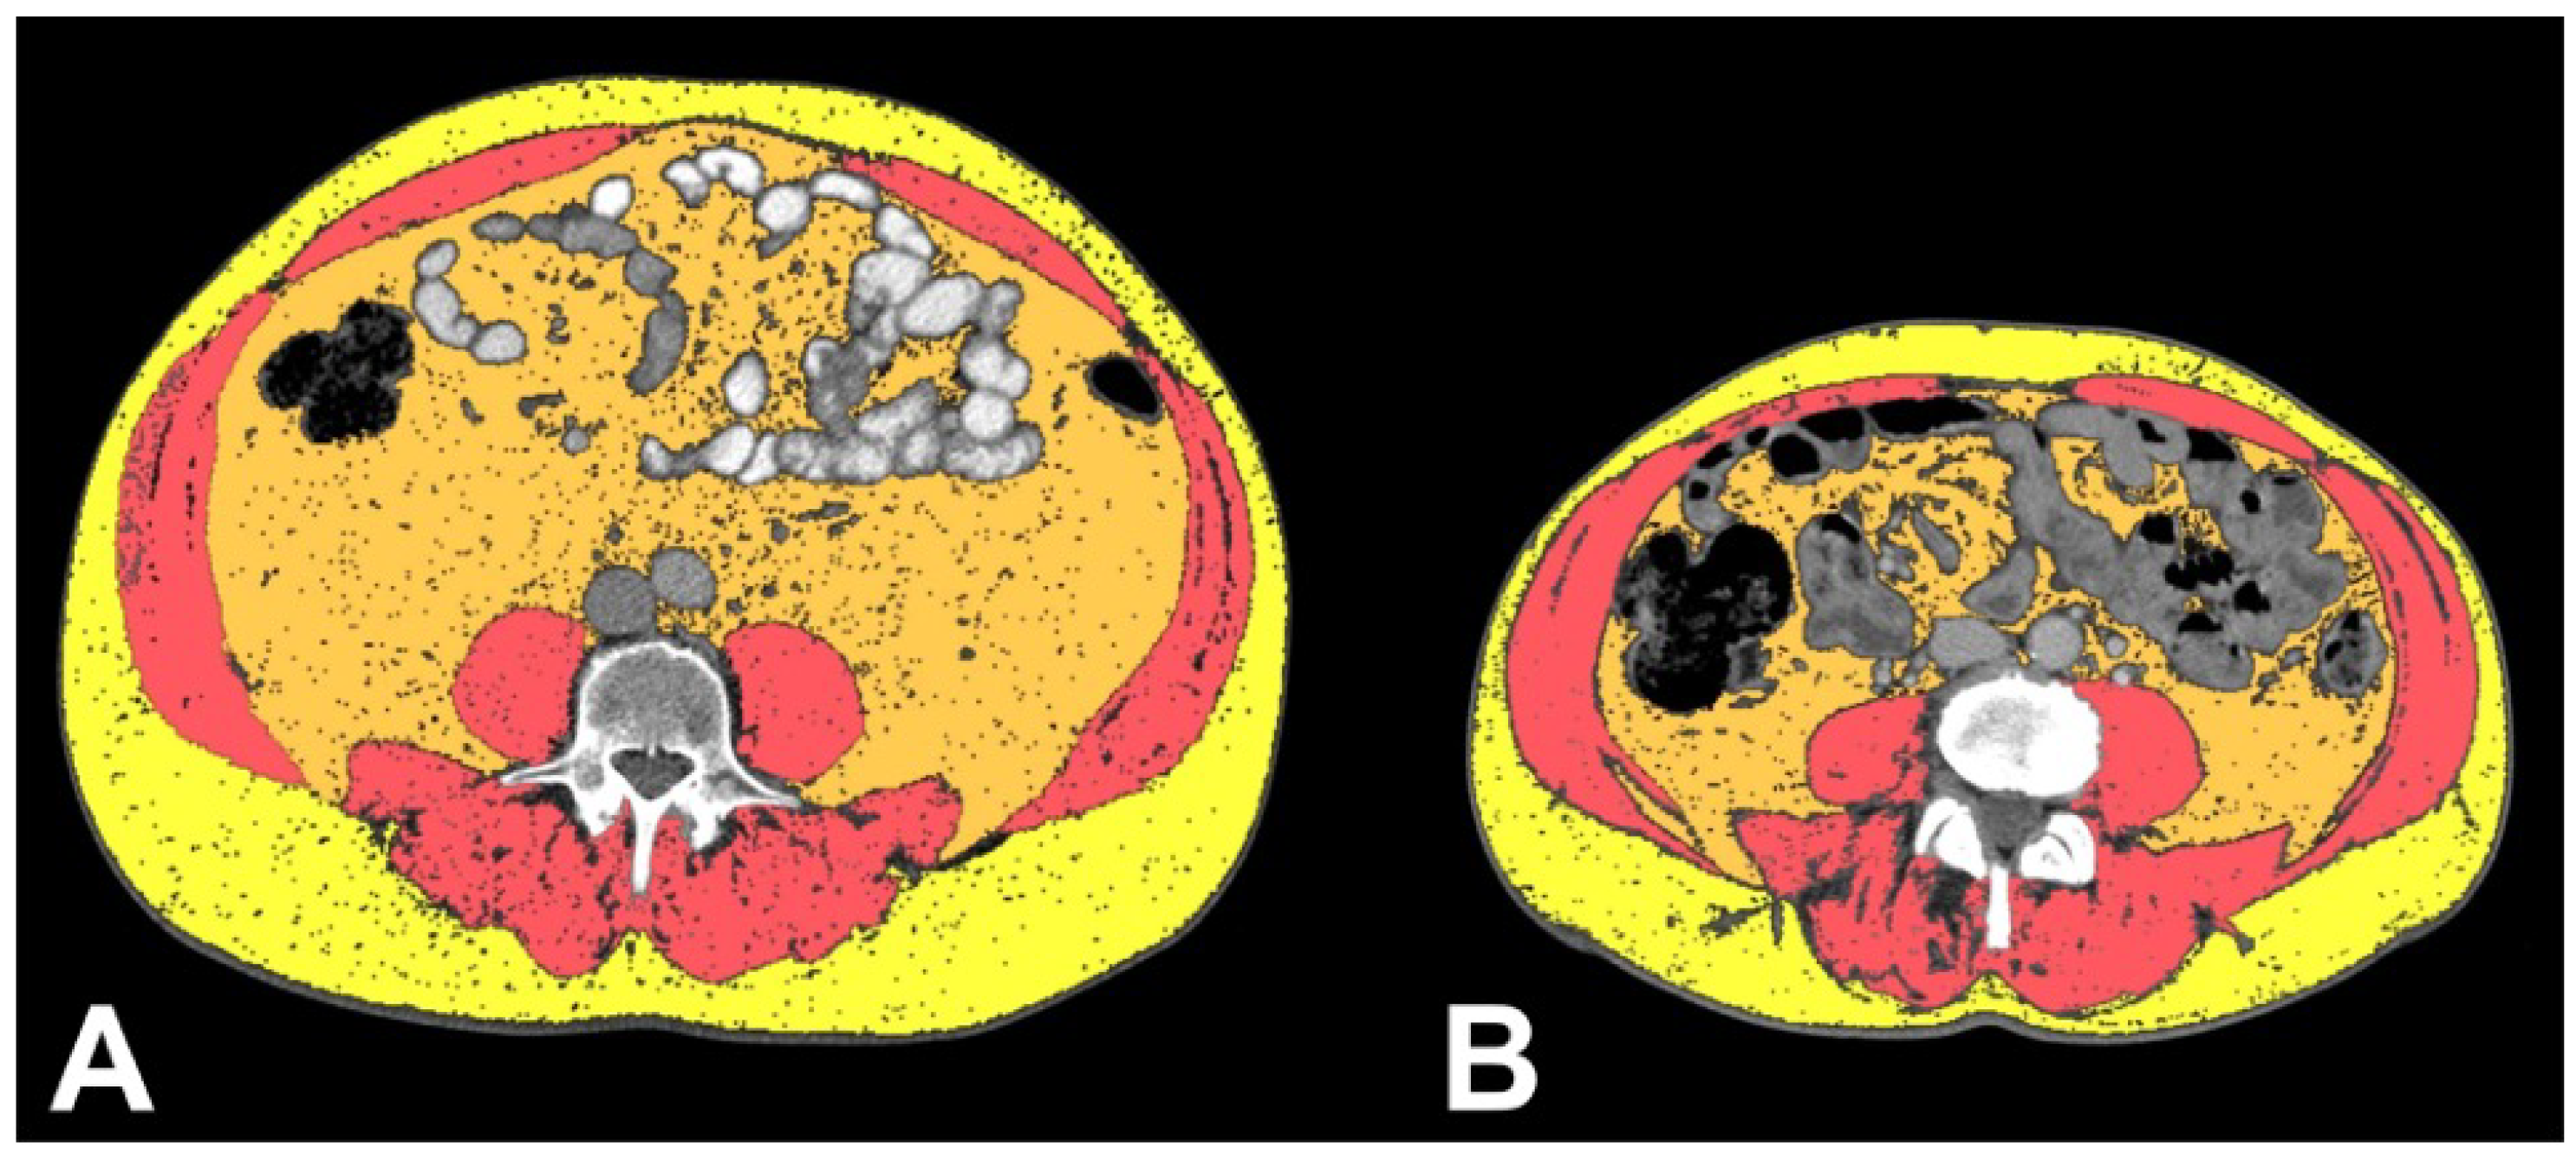

2.2. CT Analysis

3.2. Body Composition